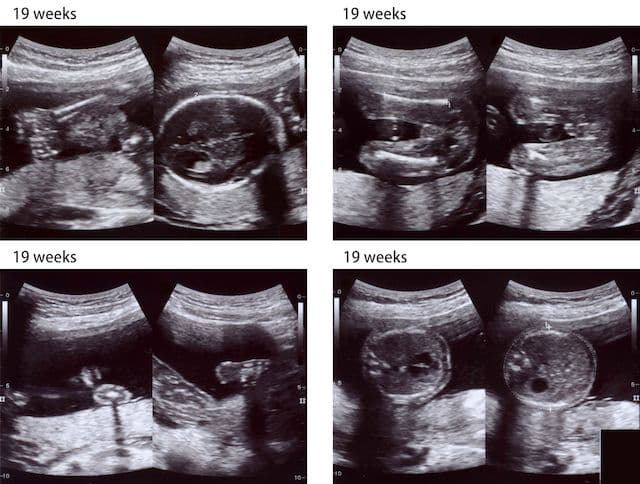

The fetal head circumference is measured during pregnancy and then compared to certain normal curves. Microcephaly is diagnosed when the head circumference falls below 2 standard deviations of the norm. Calculate the fetal head circumference here.